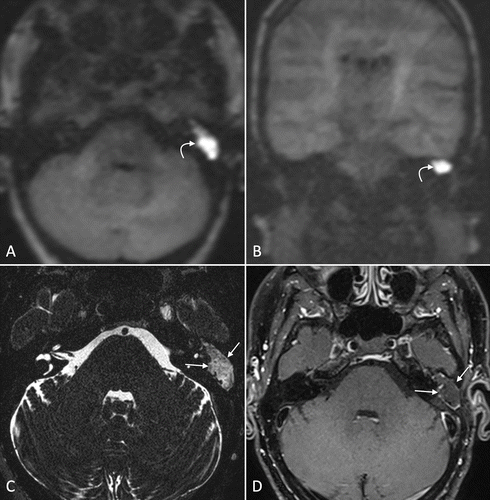

The ear is one of the main organs that are responsible for balance and hearing. The problems in the internal structure of the ear lead to hearing-related disorders.  MRI Screening of the ear is an imaging procedure that is used to view the structure of the internal ear. To diagnose the problem/ disorders related to the internal ear, this scan is usually recommended.

Why is an MRI Screening of the Ear Done?

You may be asked to undergo an MRI screening of the ear to help in the diagnosis of the various conditions. This procedure gives a detailed picture of the entire ear and helps the doctor plan the treatment.

• Serious illnesses like tinnitus, unilateral hearing loss, and otosclerosis. Meniere disease,  tumors, multiple sclerosis, and internal auditory canal.